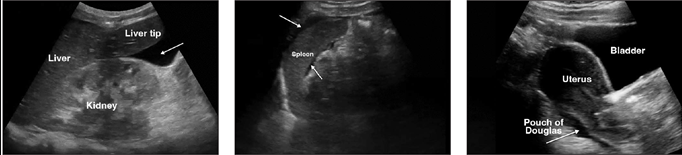

Diagnosis

Primary peritonitis is diagnosed by:

- Clinical suspicion in patient with ascites and signs of infection

- Paracentesis with ascitic fluid cell count ≥250 PMN/mm³

- Exclusion of a primary intraabdominal source of infection (clinical exam, imaging if needed)